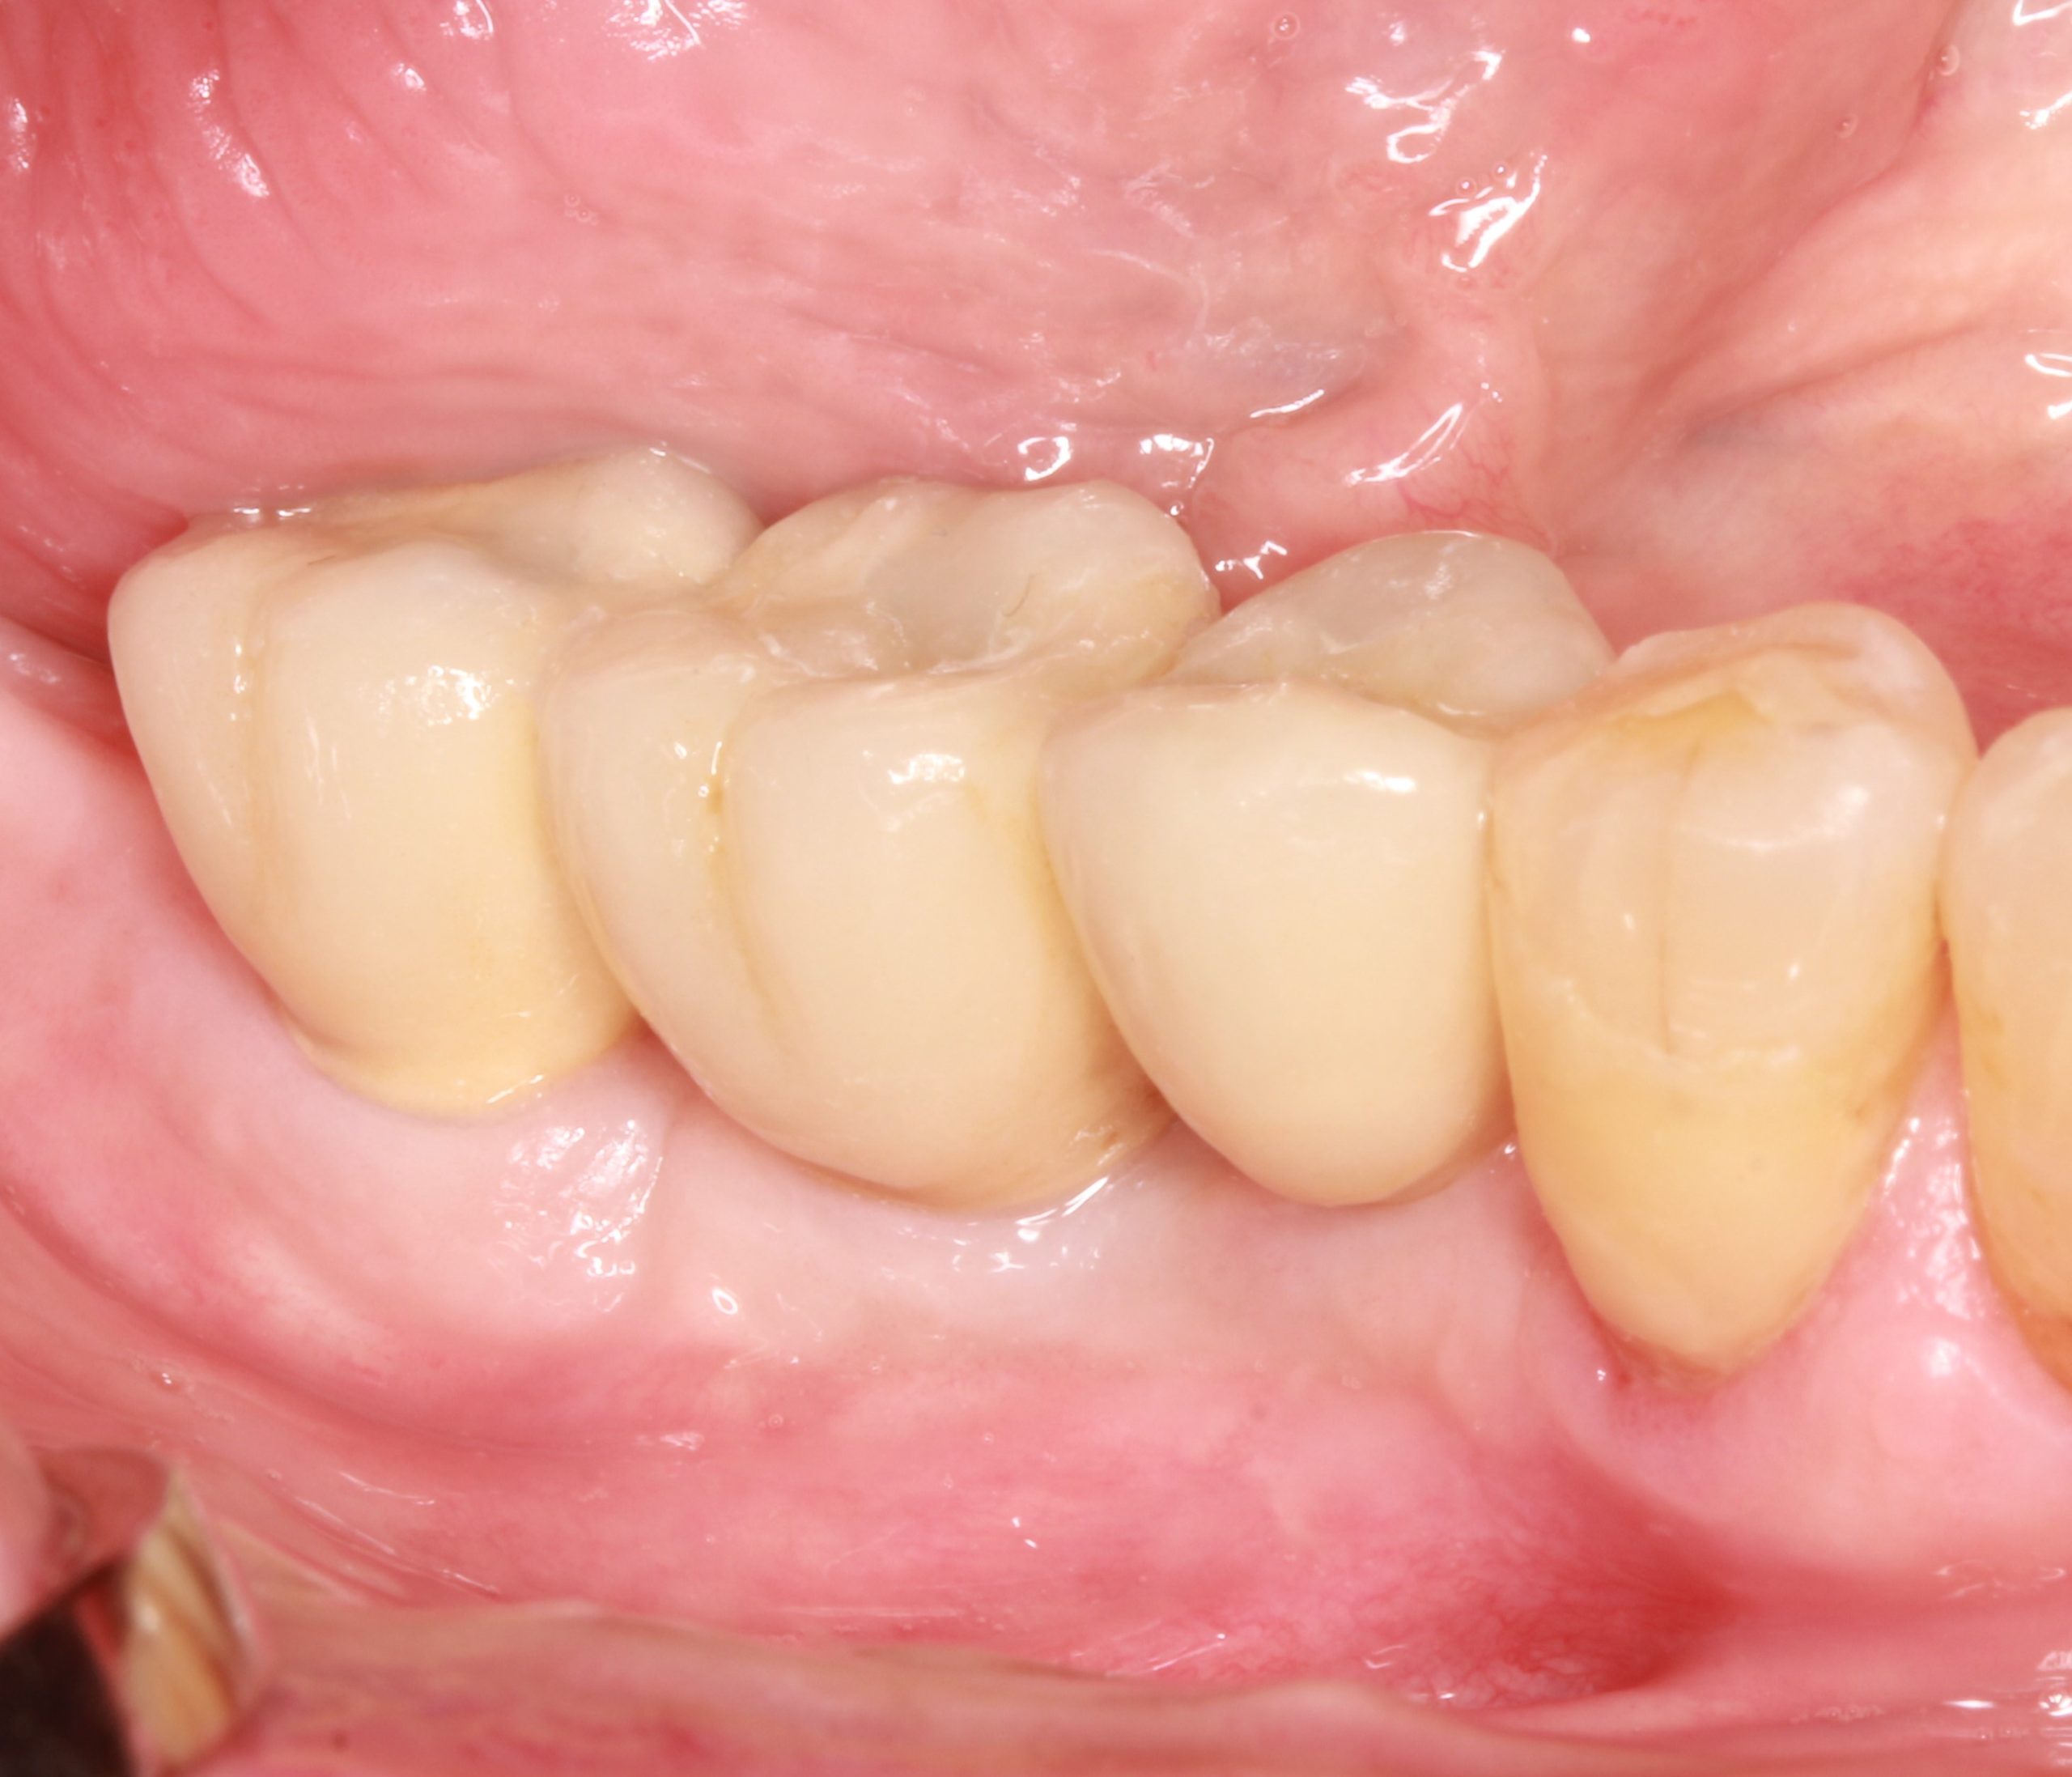

Eine festsitzende verschraubte metallkeramische Zahnbrücke wurde entworfen. Die Anprobe der Suprakonstruktion zeigt, dass sie richtig sitzt.

Der finale Zahnersatz wurde im Patientenmund verschraubt. Die Erwartungen des Patienten auf ein funktionelles und ästhetisches Ergebnis, das langfristig stabil und nachhaltig ist, wurden erfüllt.